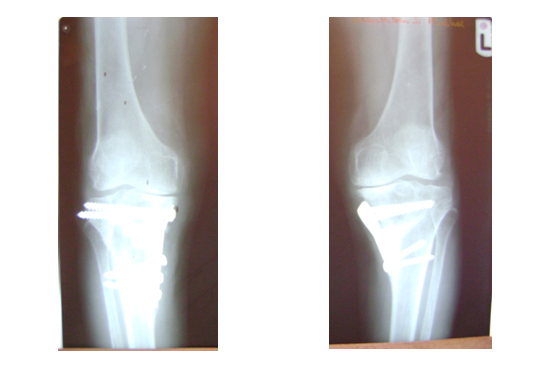

HTO

Rameshwar

Rashilaben

Shantaben